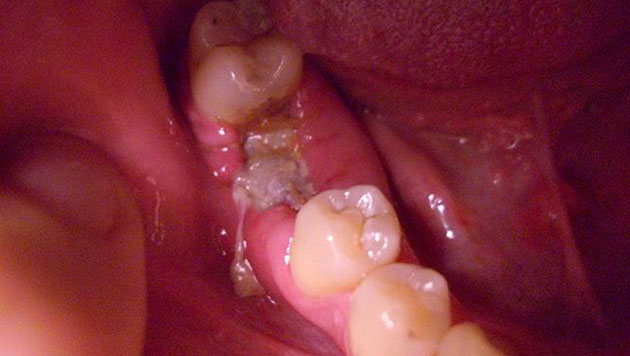

Отдавать болезненными ощущениями в скулу может даже тогда, когда имеет место обычный кариес или пульпит, периодонтит, стоматит или альвеолит, возникший вследствие удаления зуба. Ведь все органы челюстно-лицевого аппарата расположены в опасной близости друг от друга.

Хуже, когда простое стоматологическое заболевание долго оставалось невылеченным и инфекция начала распространяться дальше, дойдя до скуловой области лица. Тогда у вас уже могут болеть скулы от более серьезной патологии – остеомиелита. Заболевание поражает костную ткань челюсти, вызывая ее нагноение и некроз, сопровождается общим ухудшением самочувствия, поднимается температура тела, лицо может опухнуть и деформироваться.

«Остеомиелит верхней челюсти наблюдается во врачебной практике значительно реже, чем нижней. Тем не менее, заболевание считается очень опасным, т.к. его несвоевременное или неправильное лечение может привести к перелому челюсти, к сепсису, к поражению внутренних органов, к легочной недостаточности, флегмоне. Поэтому его необходимо лечить хирургически, дополнительно применять противовоспалительную терапию, антибиотики, лечить подвергшиеся патологическому процессу соседние органы и удалять пораженные зубы», – поясняет Цориева Э.О., терапевт, хирург.

Остеомиелит бывает разных видов: травматический, лучевой (возникает на фоне появления злокачественных раковых опухолей), гематогенный (инфекция попадает через кровь от соседних пораженных органов). Но чаще всего заболевание носит одонтогенный характер, т.е. является следствием запущенных кариеса, пульпита и других стоматологических проблем.

Остеомиелит

Причиной остеомиелита челюсти чаще всего становятся стоматологические болезни – запущенный кариес, пульпит, периодонит, альвеолит или киста на корне зуба. Попадание инфекции в кость челюсти при этом происходит именно через инфицированную пульпу или зубной корень.

Патогенные микроорганизмы могут проникать в кость из очагов поражения при фурункулезе, гнойном отите, дифтерии и скарлатине. Травматическая форма остеомиелита возникает при огнестрельном ранении и переломе челюсти.

Чаще всего диагностируется одонтогенный остеомиелит – одно из осложнений зубных патологий

При остром течении сначала появляются симптомы общей интоксикации – повышение температуры тела, слабость, головная боль, потеря аппетита. Несмотря на то, что источником боли является конкретный зуб, болевой синдром быстро распространяется на соседние области – глаз, ухо и висок.

Характерным симптомом как острого, так и хронического остеомиелита является подвижность зубов. При этом расшатывается не только больной зуб, но и близлежащие, здоровые. Прогрессирование патологии приводит к трудностям с открыванием и закрыванием рта, глотанием и дыханием.

При появлении признаков остеомиелита необходимо как можно скорее обратиться за врачебной помощью, чтобы избежать дальнейших осложнений: менингита, энцефалита, абсцесса головного мозга или легкого, сепсиса.